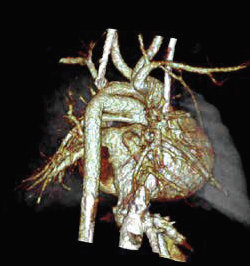

CT Excellence in:

Vascular Imaging

Exams we offer include : Run-offs, Dissection, Stent Planning & Evaluation, Pre-& Post-Carotid Surgery and CT Angiography

Neurological Imaging

Exams we offer include : Vascular Assessment, Neuro Infections & Abscesses (e.g.Encephalitis), Stroke Evaluation, Pre- and Post-Surgical Planning, Neural Neoplasms and Spinal Cord Disorders